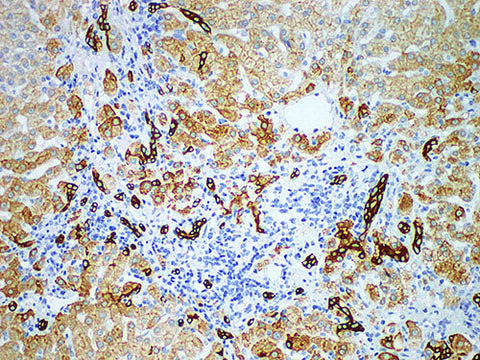

CK8 Monoclonal Antibody

Applications IHC-P

Tissue Specificity Liver cancer

Cytokeratin 8 (CK8) is a high molecular weight B-type cytokeratin, which mainly marks non-squamous epithelium. Therefore, CK8 is mainly used to identify adenocarcinoma and ductal carcinoma. Generally, CK8 is not expressed in squamous carcinoma. It has been reported that CK8 and CK18 are mainly expressed in HCC.